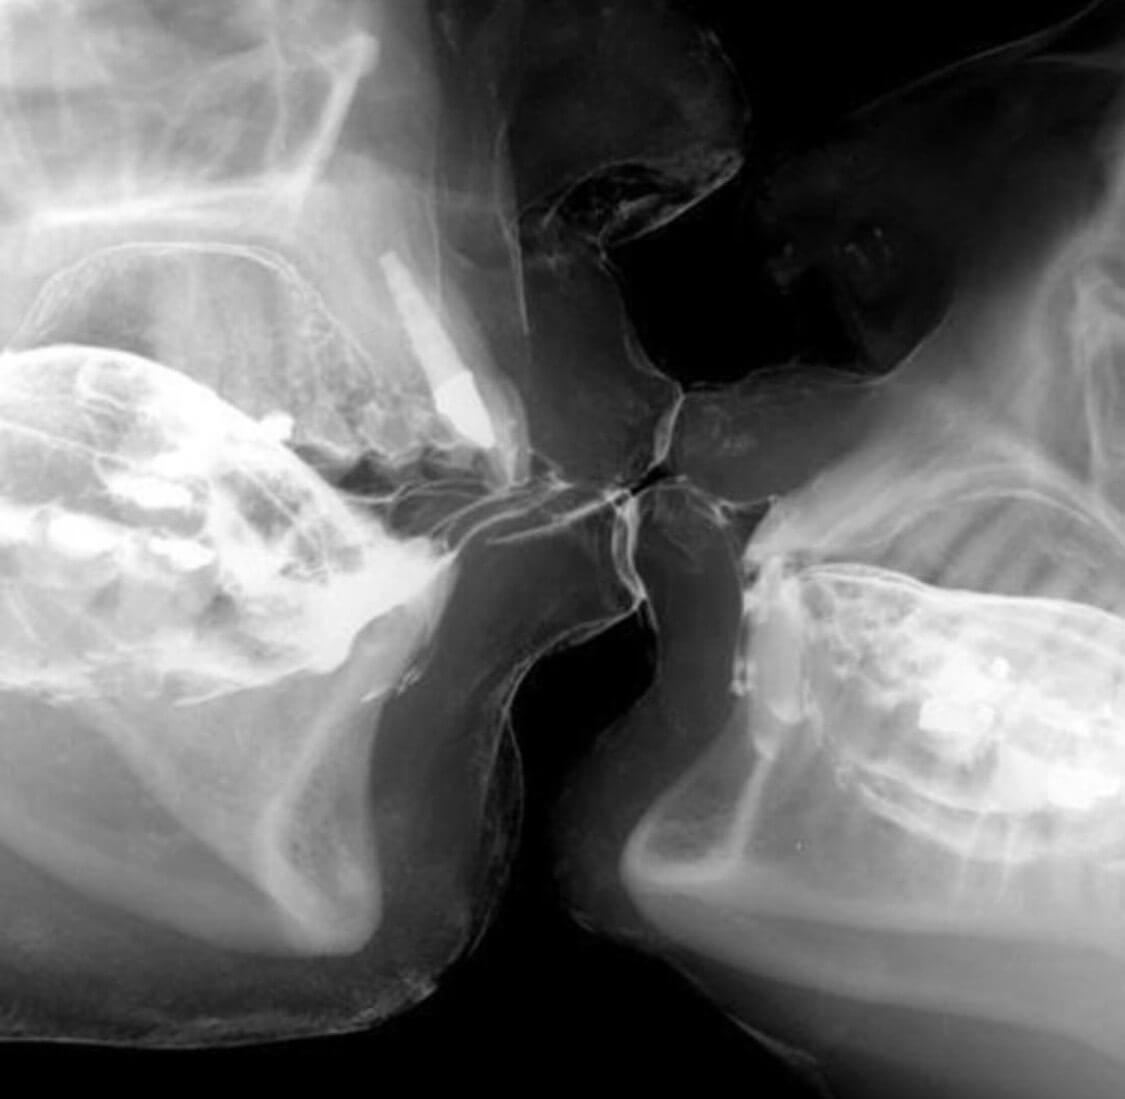

The techniques and equipment available in dentistry continue to evolve at an amazing pace. Read on in this section to learn about just a sample of some of the technology available at our office.